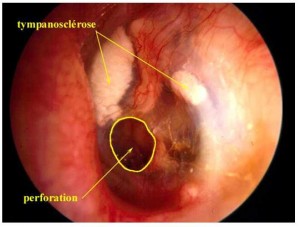

Perforation tympan, poche de rétraction : les pathologies fréquentes du tympan

Tympanoplastie : traitement chirurgical d’une pathologie du tympan ou de l’oreille moyenne.

Technique consistant à refaire chirurgicalement le tympan.

Cette opération remédie aux lésions d'une cicatrice d'une partie de la membrane du tympan et parfois de la quasi totalité du tympan (consécutive à une otite chronique en particulier). Elle consiste à faire une greffe de peau ou d'aponévrose (membrane fibreuse enveloppant les muscles en les séparant les uns des autres) sur l'orifice consécutif à la perforation du tympan.

Le plus souvent, on pratique parallèlement une réparation des lésions de la chaîne des

osselets.

Le tympan est une membrane permettant la transmission des vibrations à l'oreille interne par l'intermédiaire de 3 osselets : le marteau, l'enclume, l'étrier.

La tympanoplastie est pratiquée sous anesthésie générale et nécessite entre 48 heures et une semaine d'hospitalisation.

La myringoplastie proprement dite est la technique la plus courante des tympanoplasties. Son but est la réparation d'une perforation du tympan résultant d'une otite (inflammation de l'oreille) ou d'un traumatisme. Cette réfection ou réparation chirurgicale s'opère au moyen d'un greffon. Généralement, il s'agit d'un fragment de la membrane fibreuse enveloppant le muscle temporal, c'est-à-dire le muscle situé sous le cuir chevelu au niveau de la tempe.

L'ossiculoplastie a pour but de réparer la chaîne des osselets (voir ci-dessus). Celle-ci présente une lésion le plus souvent la suite d'une otite et plus rarement après une fracture ou une luxation des osselets.

Ces deux opérations nécessitent une surveillance et un suivi d'environ 5 à 10 jours.